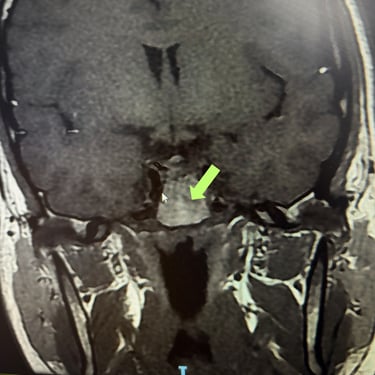

Tumor Selar Hemorrágico: Tratamiento Endoscópico Transesfenoidal.

El tumor selar hemorrágico, también conocido como apoplejía hipofisaria, es una urgencia neuroquirúrgica que puede manifestarse con cefalea intensa, alteraciones visuales y compromiso hormonal agudo. El abordaje mediante cirugía endoscópica transesfenoidal permite un acceso directo y mínimamente invasivo a la región selar, facilitando la evacuación del componente hemorrágico y la resección del tumor. Esta técnica ofrece una adecuada descompresión del quiasma óptico, preservación de estructuras neurovasculares y una recuperación más rápida. El tratamiento oportuno es clave para mejorar el pronóstico neurológico y visual del paciente.